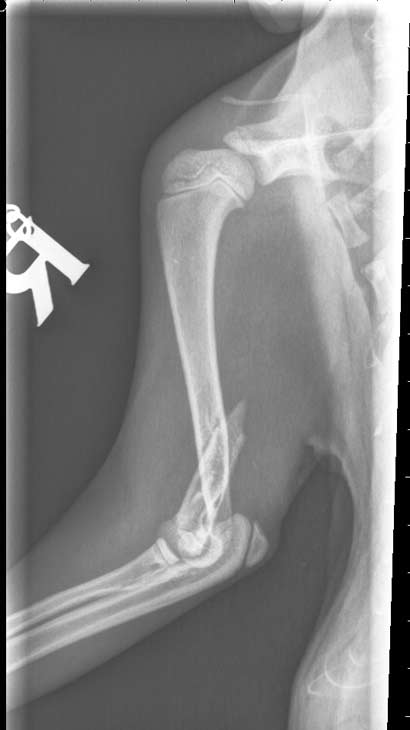

Glück im Unglück hatte Looping:

...... verletzt umherirrend wurde er gefunden und von Menschen, die sofort gehandelt haben, im Tierheim abgegeben. Das war sein Glück, wir möchten uns erst gar nicht vorstellen, was passiert wäre, hätte man ihn seinem Schicksal überlassen. Noch am gleichen Tag wurden alle Hebel in Bewegung gesetzt um dem kleinen, schwarzen Etwas zu helfen und ihn zu einem Tierarzt zu bringen.

Dank eines aussergewöhnlichen Einsatzes konnte er noch am Heilig Abend geröntgt werden, doch leider war die Diagnose erschreckend: ganz fiese Brüche in beiden !! Vorderbeinen.

Der Arme musste schreckliche Schmerzen bei jeder Bewegung haben. Trotzdem ließ er alle Untersuchungen brav über sich ergehen und war geduldig und freundlich.

Nun war schnelles Handeln gefragt, um dem lieben Kater zu helfen.

Noch an den Weihnachtstagen liessen wir Looping in eine chirurgische Klinik bringen, damit er schnellstmöglich operiert und seine Frakturen entsprechend versorgt werden konnten. Die Brüche sind wohl durch einen Sturz/Sprung von extremer Höhe entstanden, vielleicht durch den Sturz von einem Balkon?? (Leider haben immer noch viele Leute ungesicherte Balkone und unterschätzen die Neugierde und den natürlichen Jagdinstinkt von Katzen wenn z.B. ein Vogel vorbei fliegt)